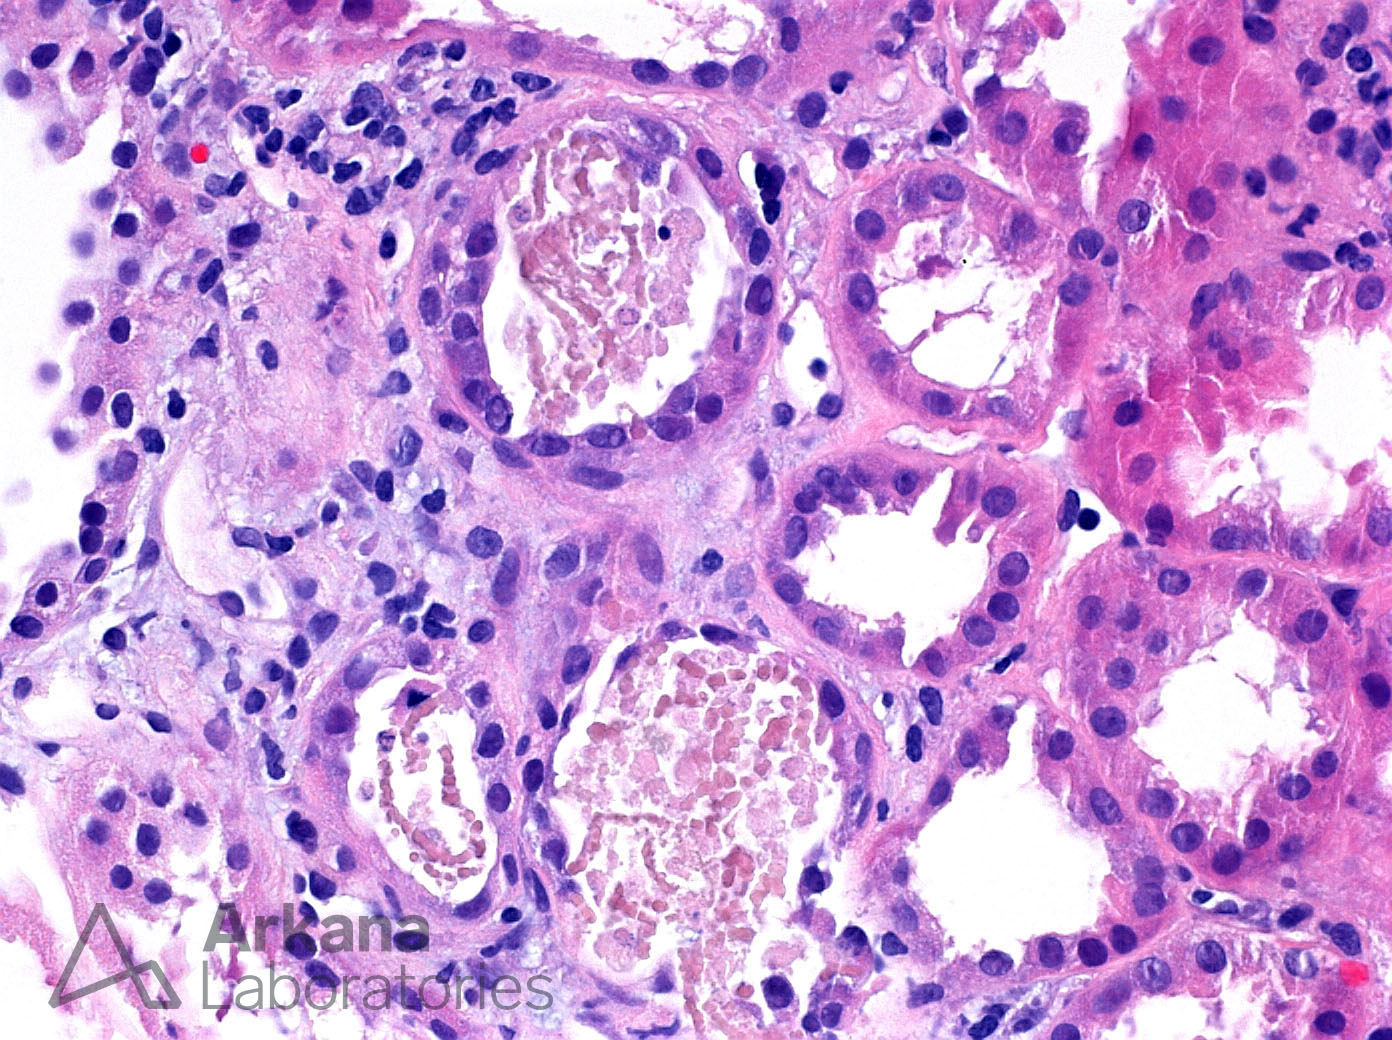

Though our patient did not require a kidney biopsy as the diagnosis was clear from the available data, we would expect to see myoglobin casts in the tubules as shown below (review the different slide preparations here).

Immunohistochemistry (IHC) stains can be done to identify specific antigens. The IHC stain for myoglobin below confirms the presence of myoglobin within the tubule.